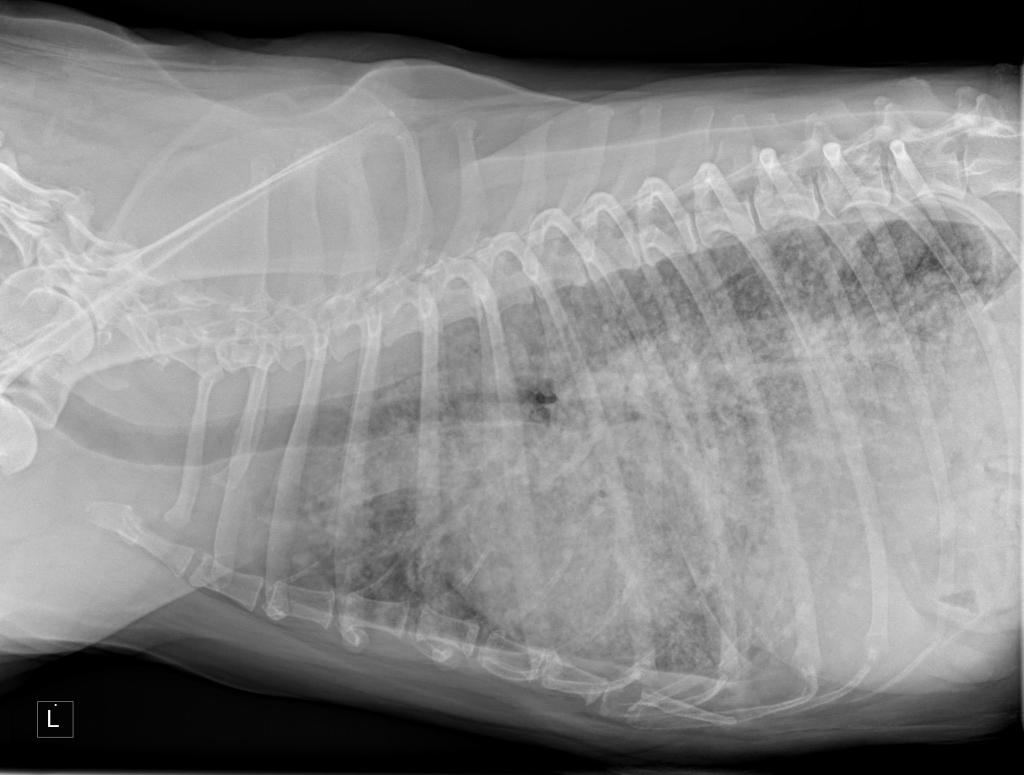

But the most important indicator of it being something other than a fungal infection was that the xray showed Hazel’s lungs to be worse.

My photograph of the clinic's screen display.

This can be more readily seen if I publish the xray image of yesterday and the image taken on the 15th April; see below.

Xray image as of the morning of May 12th, 2016.

One of the radiographs taken of Hazel.

One of the radiographs taken of Hazel 15th April, 2016.

Despite not truly understanding these images both Jean and I quickly thought the top one, taken yesterday, showed a decline in Hazel’s lungs compared to the lower one, taken on the 15th April.